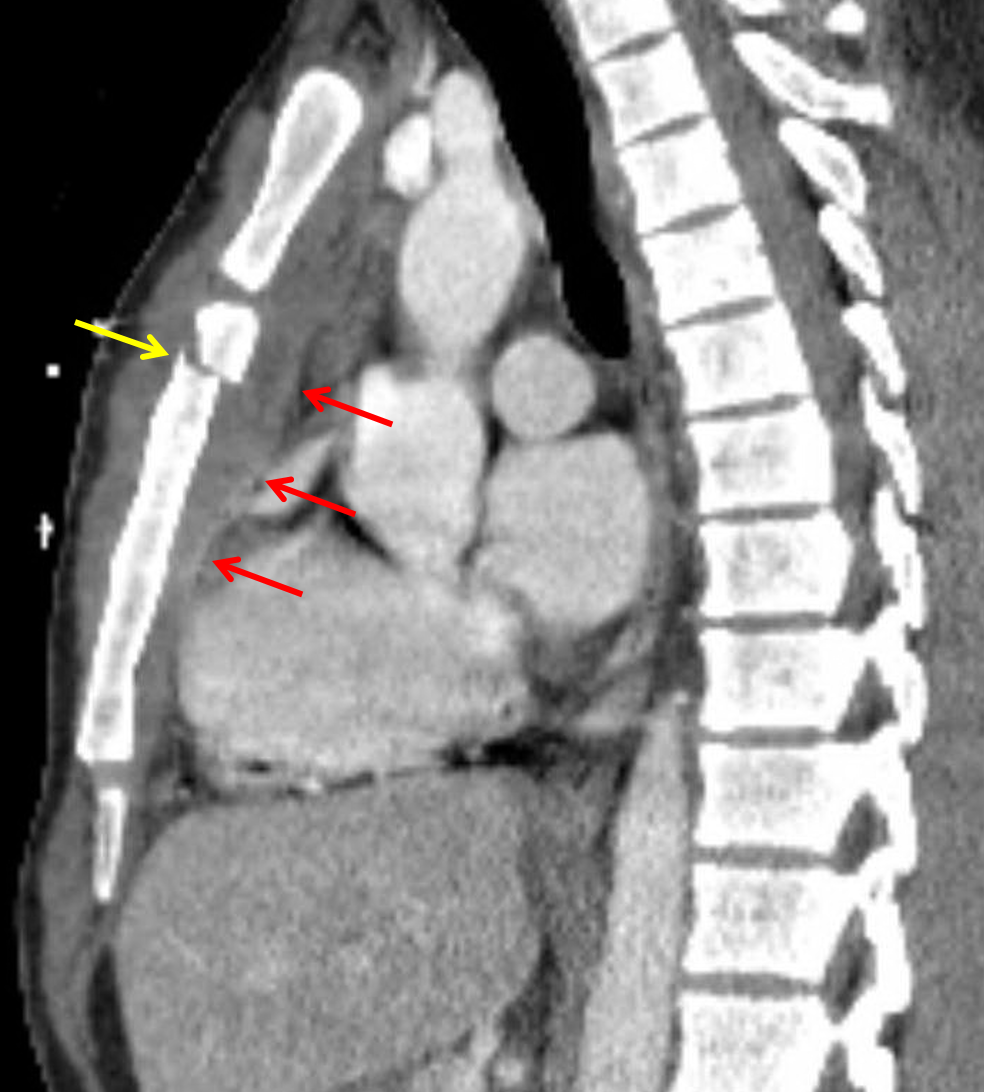

Sample ReportAcute oblique upper sternal body fracture with slight offset and a subjacent mediastinal hematoma measuring 1.5 cm in anteroposterior thickness. No direct evidence of aortic trauma or active hemorrhage.